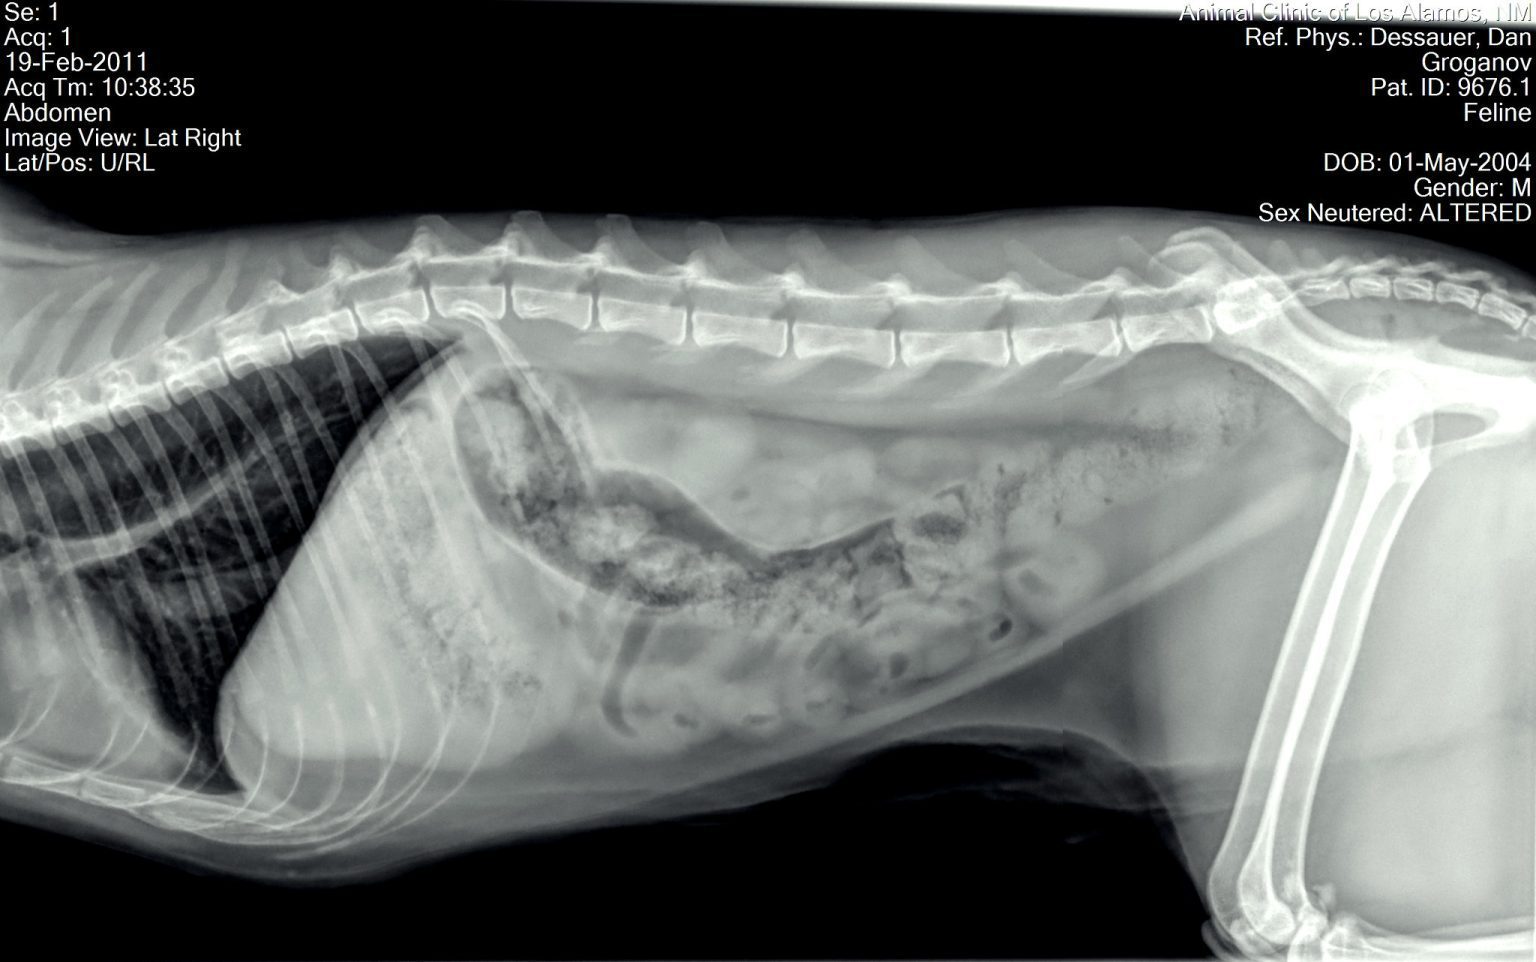

From pet-how.com

How Long Can a Cat Go Without Pooping? (Answered!) How Long Can A Cat Go Without Pooping After Surgery Our guide will help you understand the basics of looking after your cat after an operation or dental procedure, what to expect after neutering a cat, how to keep your cat from jumping. Before we get into why a cat is not pooping but acting normal, we need to establish how long a cat can go without pooping. This is. How Long Can A Cat Go Without Pooping After Surgery.